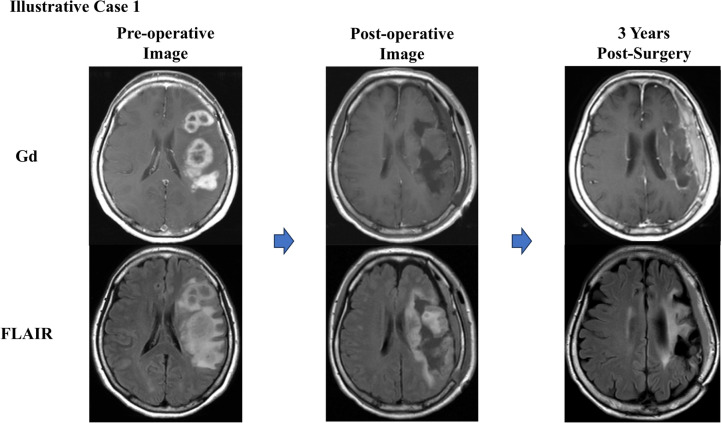

Abstract Image